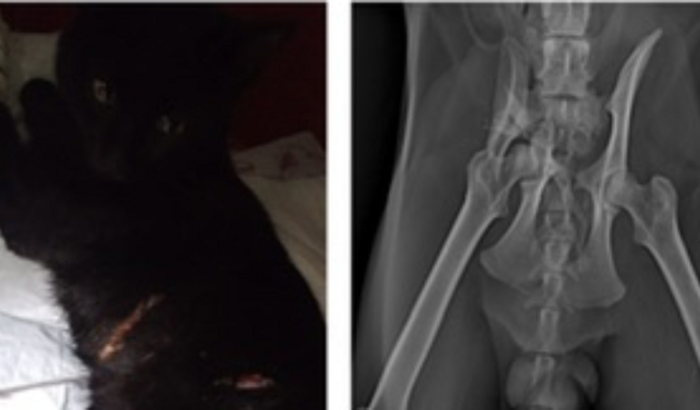

Oiee Pessoal , esse gatinho lindo se chama Pretinho e foi encontrado muito machucado devido a um trauma que sofreu . Foi encaminhado para o veterinário e o diagnóstico infelizmente não foi bom . Ele precisa fazer uma cirurgia urgente pois fraturou o ílio , pubis e ísquio. Quem puder por favor ajudar , todo valor é muito importante. Desde já muito obrigada .